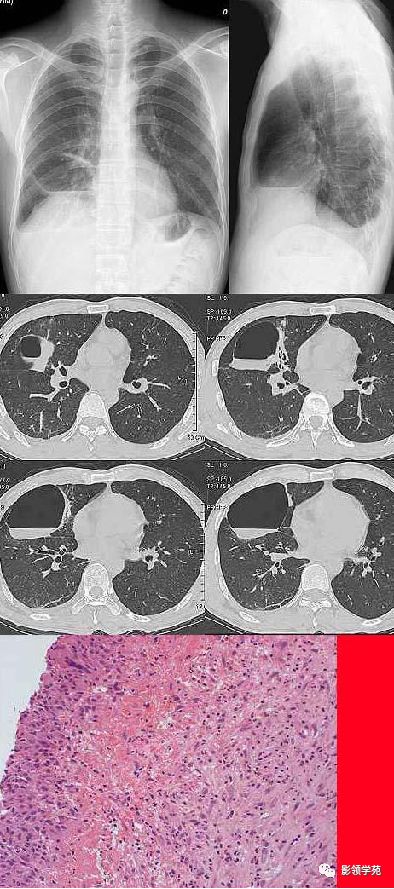

肺实变,肺实变ct图片

肺实变后支气管充气征

肺大泡合并感染: 肺大泡周围肺组织实变,表现为片状影或肺实变影内有

肺实变,大片阴影,肺量增加

肺实变ct图片

肺实变图片

肺实变x线表现图片